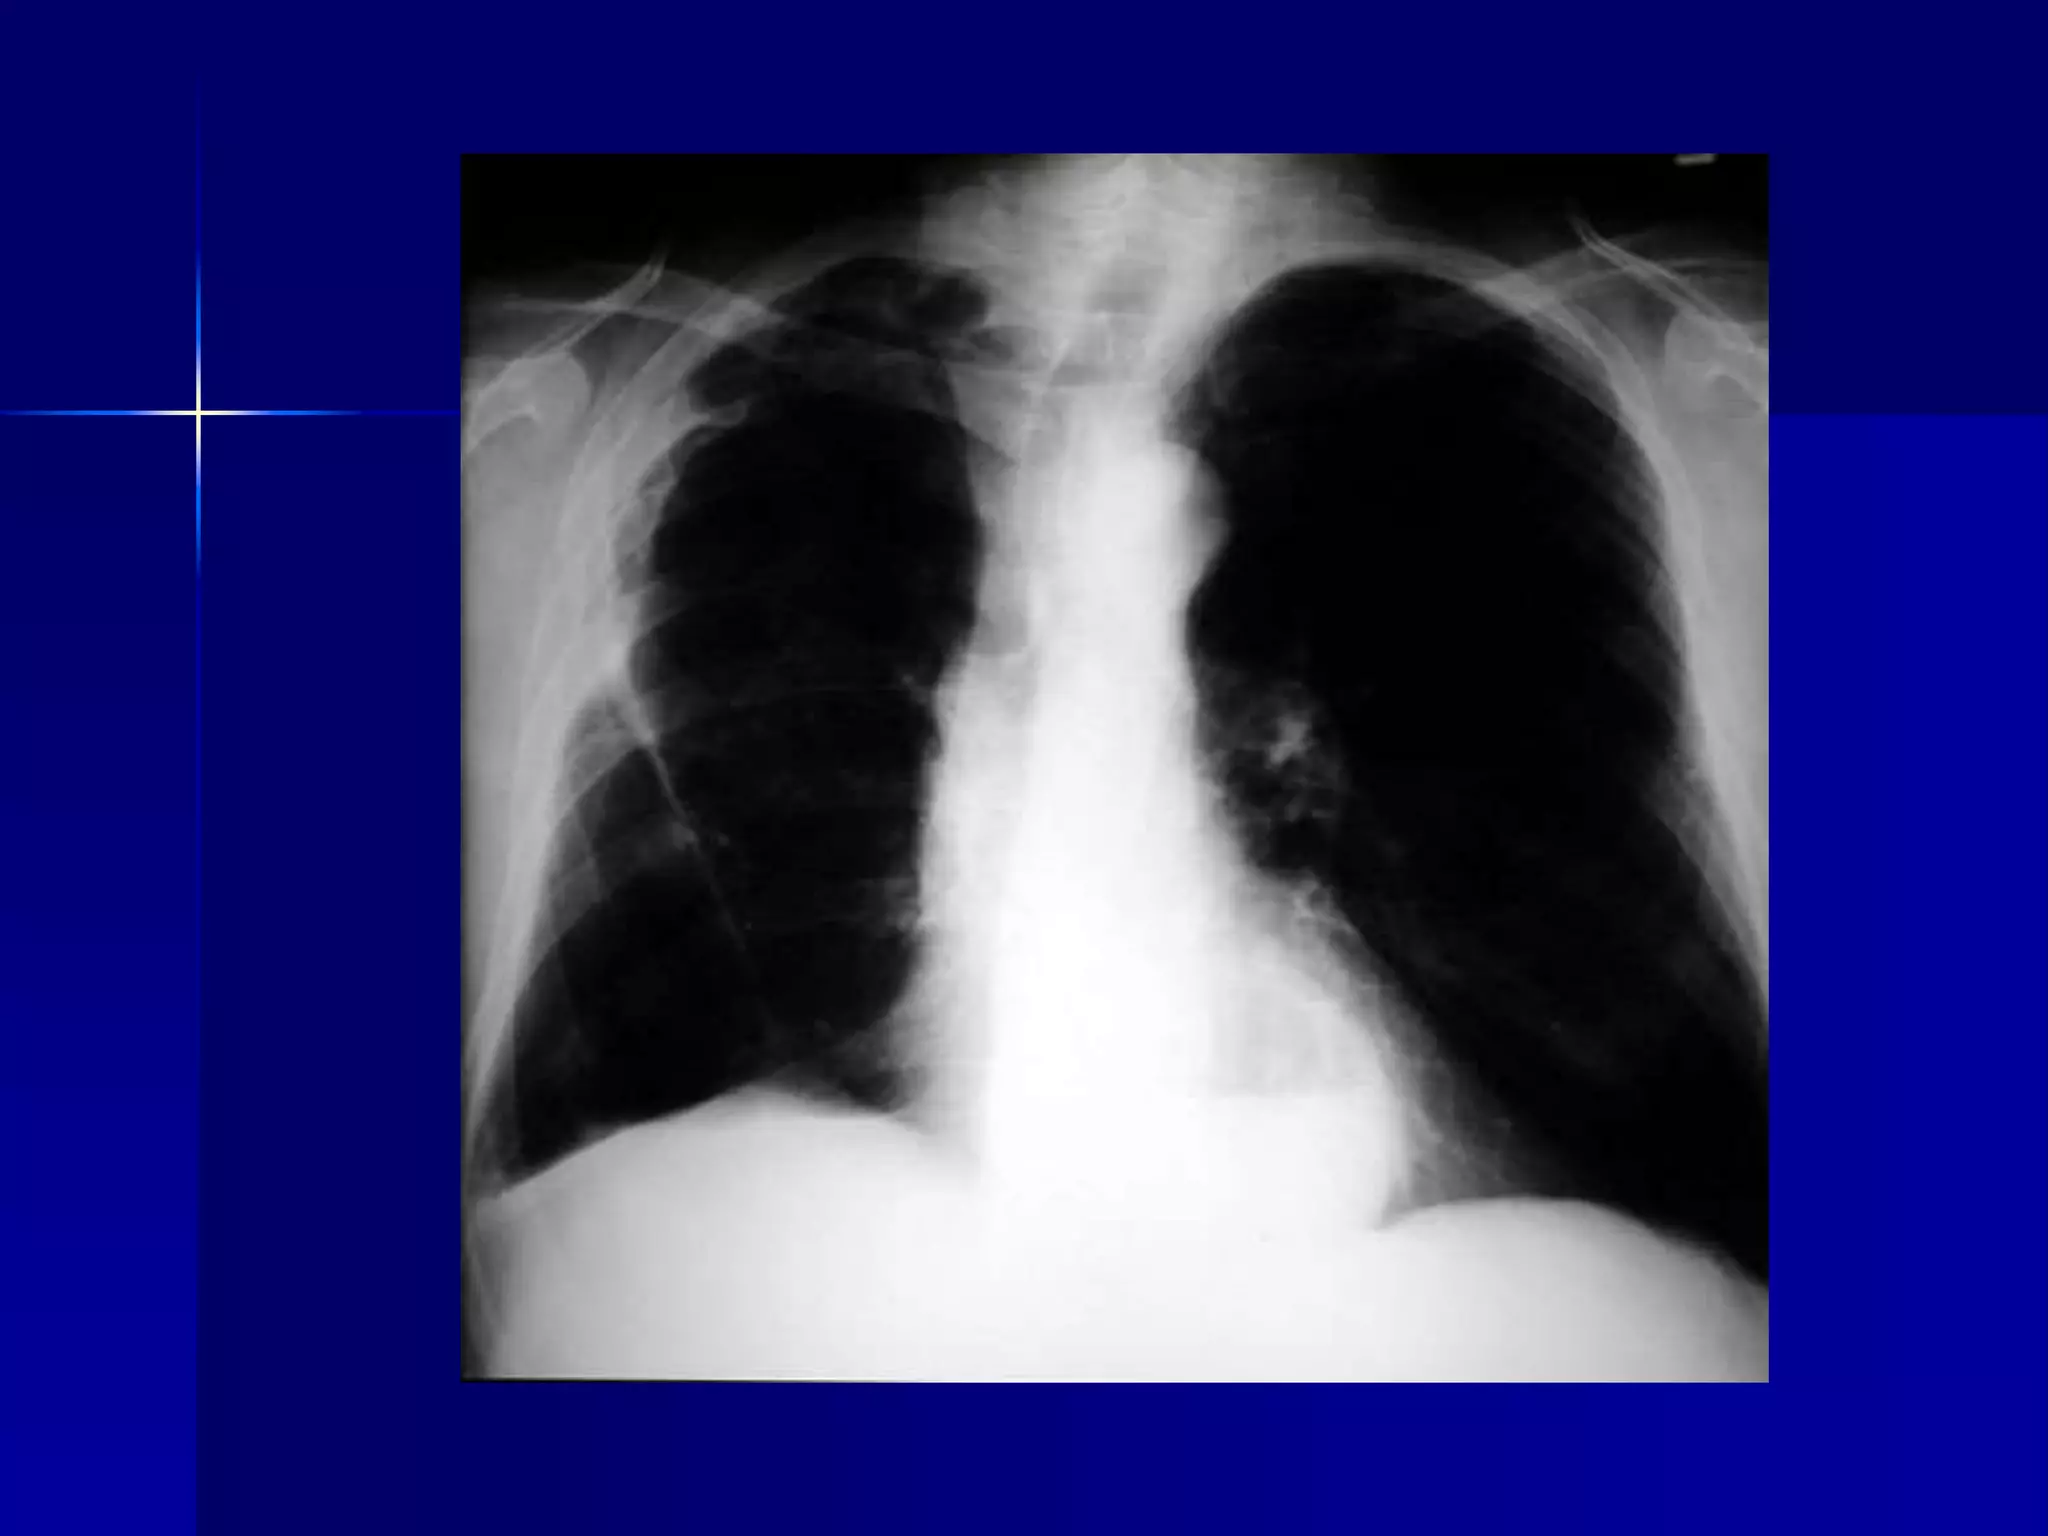

Atelectasis Left Lung

 Homogenous density left hemithorax

 Mediastinal shift to the left

 Diaphragmatic and heart silhouette

are not identifiable

 Atelectasis Left Lower Lobe

 Inhomogeneous cardiac density

 Triangular retrocardiac density

 Left hilum pulled down